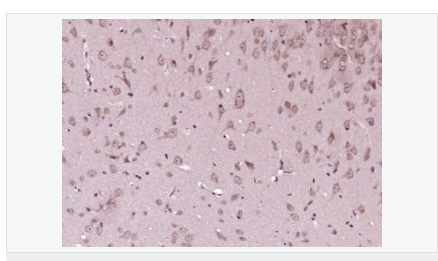

交叉反應:Human,Mouse,Rat(predicted:Dog,Pig,Cow,Horse,Rabbit,Sheep,GuineaPig) 推薦應用:WB,IHC-P,IHC-F,IF,Flow-Cyt,ELISA

| 產品應用 | WB=1:500-2000 ELISA=1:5000-10000 IHC-P=1:100-500 IHC-F=1:100-500 Flow-Cyt=1μg/Test ICC=1:100-500 IF=1:100-500 (石蠟切片需做抗原修復) not yet tested in other applications. optimal dilutions/concentrations should be determined by the end user. |